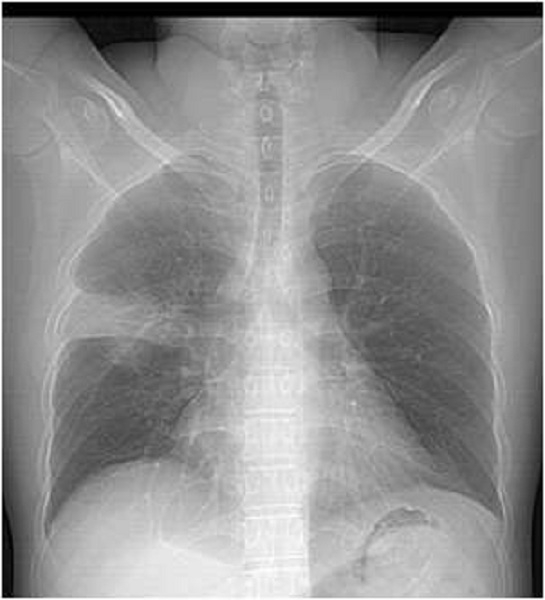

图说:新冠肺炎胸片  来源/采访对象供图(下同)

专家说,新型冠状病毒感染的肺,还是具有一定特征的。

上海市胸科医院放射科主任医师于红介绍:影像学检查必不可少,新冠肺炎的影像特征与其他病毒性肺炎相似。

早期患者多表现单发或多发小斑片影、局灶性磨玻璃影等,病灶分布以肺外周胸膜下为多。

进展期病灶增多并融合,范围扩大,密度逐渐增高,表现为多个肺叶段多灶性斑片样或弥漫性磨玻璃影及实变影。

严重者会出现“白肺”。

新型冠状病毒性肺炎进展可能很快,但也有一部分患者早期没有明显影像学表现,因此结合临床病史、接触史及实验室检查以及短期内复查非常重要。